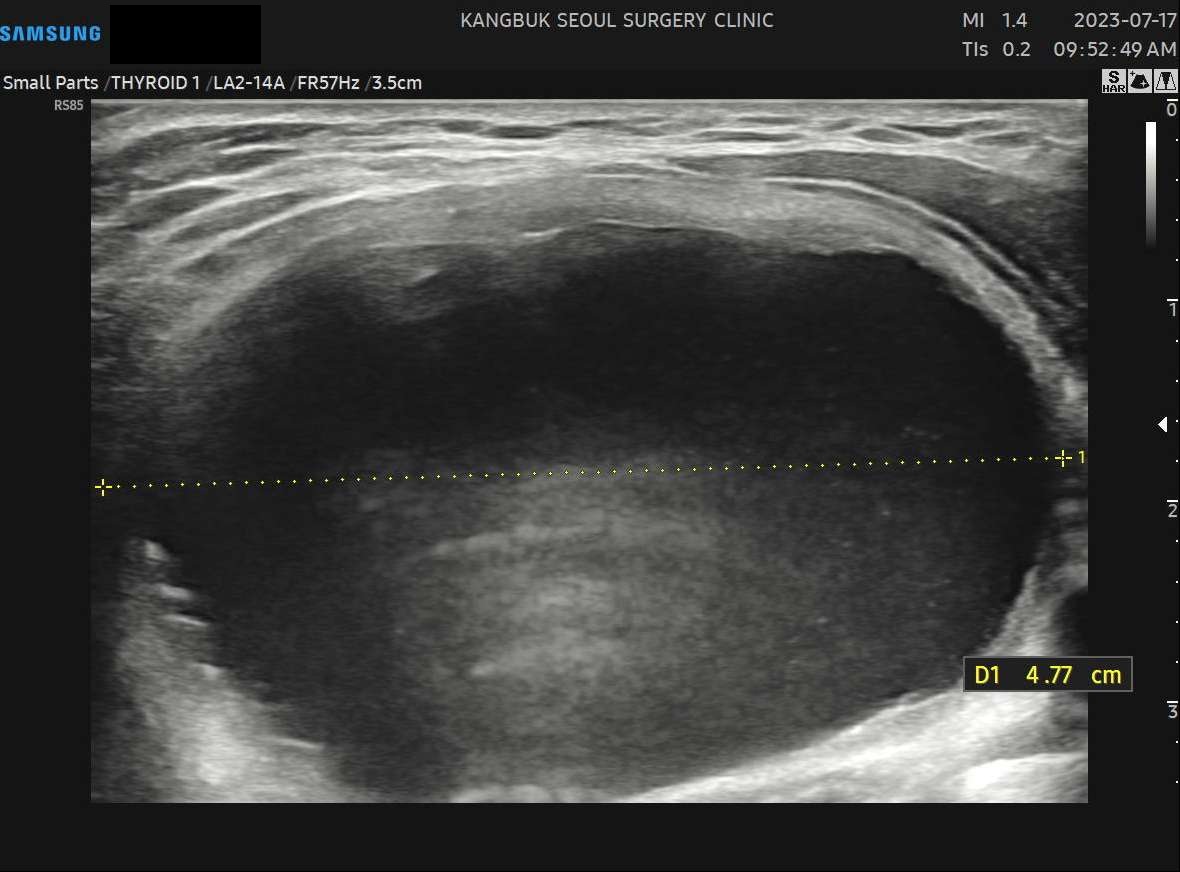

수술 전(4.77cm)